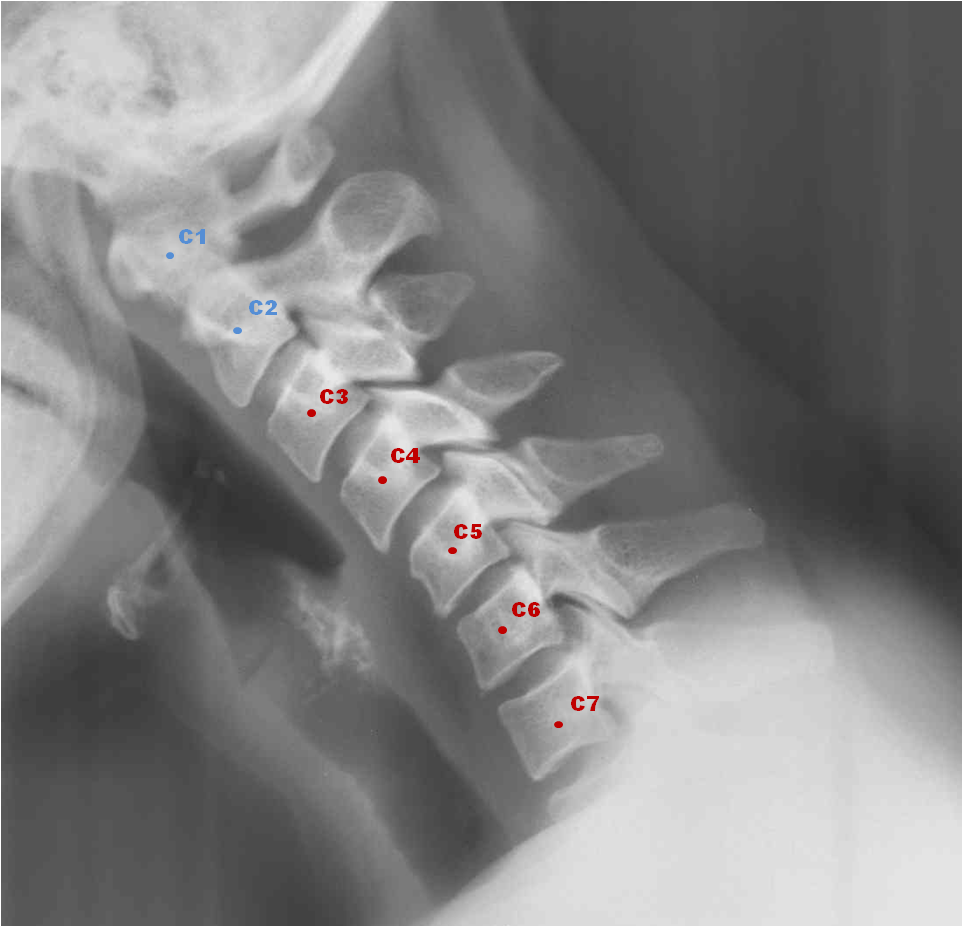

A partir de estas apreciaciones generales sobre el sentido y significado del dolor cervical, es necesario entrar en detalles más precisos porque cada una de las siete vértebras cervicales tiene un simbolismo propio y, por tanto, manifiesta conflictos diferentes.

Los problemas en las vértebras C1, C2, y C3 guardan especial relación con situaciones de desvalorización intelectual.

C1 o Atlas: Relacionada con la lengua y el cerebro. Sirve de soporte a la cabeza, la mantiene en equilibrio. Cuando vivimos las situaciones de la vida con estrechez mental o rigidez, esta vértebra reacciona perdiendo sus funciones. Se paralizará por el miedo, la negatividad y la desesperación, provocando habitualmente la aparición de dolores de cabeza y problemas que afectan al sistema nervioso.

C2 o Axis: Conectada con los órganos de los sentidos (ojos, nariz, orejas, boca – lengua). Si me aferro a mis viejas creencias y me preocupo constantemente y de forma excesiva por el futuro, esta vértebra reaccionará entrando en rigidez. Se perderá lubricación y surgirán irritación, calentamiento y dolor.

C3: Relacionada con la laringe. Cuando tenemos problemas en C3, nos volvemos irritables con respecto a una persona o una situación. También está relacionada con las mejillas, la cara y el oído exterior. Está vinculada también con los problemas de desvalorización, de contacto y de estética, como acné, granos y eccemas. Problemas en esta vértebra pueden dar lugar a daños en el rostro, así como en las orejas y los dientes.

Las vértebras C4, C5, C6 están en relación con la tiroides y, a través de ella, afectan al lenguaje y la voz, es decir, la comunicación que expreso y la que recibo. Pueden ser situaciones en las que no me permito expresar mis opiniones o cuando escucho palabras y mensajes que me causan ira e indignación. Estas situaciones pueden incrementar nuestra agresividad, por lo que se cerrarán nuestros canales de comunicación. Nos cuesta “digerir” lo que escuchamos o tendemos a darle muchas vueltas a lo que hemos escuchado o a lo que nos gustaría expresar y no expresamos. En estos casos, frecuentemente aparecen dolencias que afectan a todo el sistema de comunicación: boca, lengua y cuerdas vocales, pudiendo llegar a afectar, de manera generalizada, a todo lo que se localiza entre la boca y los hombros.

C4: Vinculada a la nariz y la boca. Se refiere a la comunicación verbal, al concepto real y concreto de las cosas. Las palabras de los acontecimientos del día a día. Muy habitual en problemas de comunicación en el trabajo.

C5: Relacionada con la faringe y las cuerdas vocales. Conflictos que se viven como injusticia.

C6: Hace referencia a las amígdalas y al cuello de forma genérica. Expresa conflictos vividos como injustos y con desvalorización.

C7: Esta última vértebra cervical guarda una especial vinculación con la tiroides, las manos, los codos, los brazos y los hombros. Cuando C7 está afectada es porque estamos o hemos estado ante conflictos de injusticia y/o de sumisión, de doblegarnos contra nuestra voluntad. Aquí entran en juego nuestros principios y valores morales, así como nuestras creencias, que harán que vivamos de manera más o menos acusada esa “cesión” forzada. Cuando somos presa de emociones intensas en la vida o tenemos miedo de ser rechazados, la vértebra C7 nos avisará.